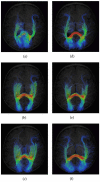

White matter fiber tractography plays a key role in the in vivo understanding of brain circuitry. For tract-based comparison of a population of images, a common approach is to first generate an atlas by averaging, after spatial normalization, all images in the population, and then perform tractography using the constructed atlas. The reconstructed fiber trajectories form a common geometry onto which diffusion properties of each individual subject can be projected based on the corresponding locations in the subject native space. However, in the case of high angular resolution diffusion imaging (HARDI), where modeling fiber crossings is an important goal, the above-mentioned averaging method for generating an atlas results in significant error in the estimation of local fiber orientations and causes a major loss of fiber crossings. These limitatitons have significant impact on the accuracy of the reconstructed fiber trajectories and jeopardize subsequent tract-based analysis. As a remedy, we present in this paper a more effective means of performing tractography at a population level. Our method entails determining a bipolar Watson distribution at each voxel location based on information given by all images in the population, giving us not only the local principal orientations of the fiber pathways, but also confidence levels of how reliable these orientations are across subjects. The distribution field is then fed as an input to a probabilistic tractography framework for reconstructing a set of fiber trajectories that are consistent across all images in the population. We observe that the proposed method, called PopTract, results in significantly better preservation of fiber crossings, and hence yields better trajectory reconstruction in the atlas space.